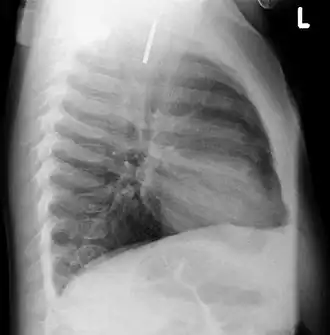

AP X ray showing a 9mm battery in the intestines -

Lateral X ray showing a 9mm battery in the intestines -